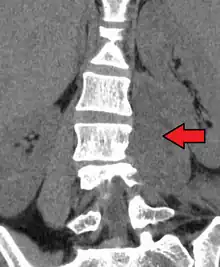

Psoas abscess is a collection of pus in the iliopsoas muscle compartment.[1][2] It can be classified into primary psoas abscess (caused by hematogenous or lymphatic spread of a pathogen) and secondary psoas abscess (resulting from contiguous spread from an adjacent infectious focus).[2]

Psoas abscess may be caused by lumbar tuberculosis. Owing to the proximal attachments of the iliopsoas, such an abscess may drain inferiorly into the upper medial thigh and present as a swelling in the region. The sheath of the muscle arises from the lumbar vertebrae and the intervertebral discs between the vertebrae. The disc is more susceptible to infection, from tuberculosis and Salmonella discitis. The infection can spread into the psoas muscle sheath.[3]